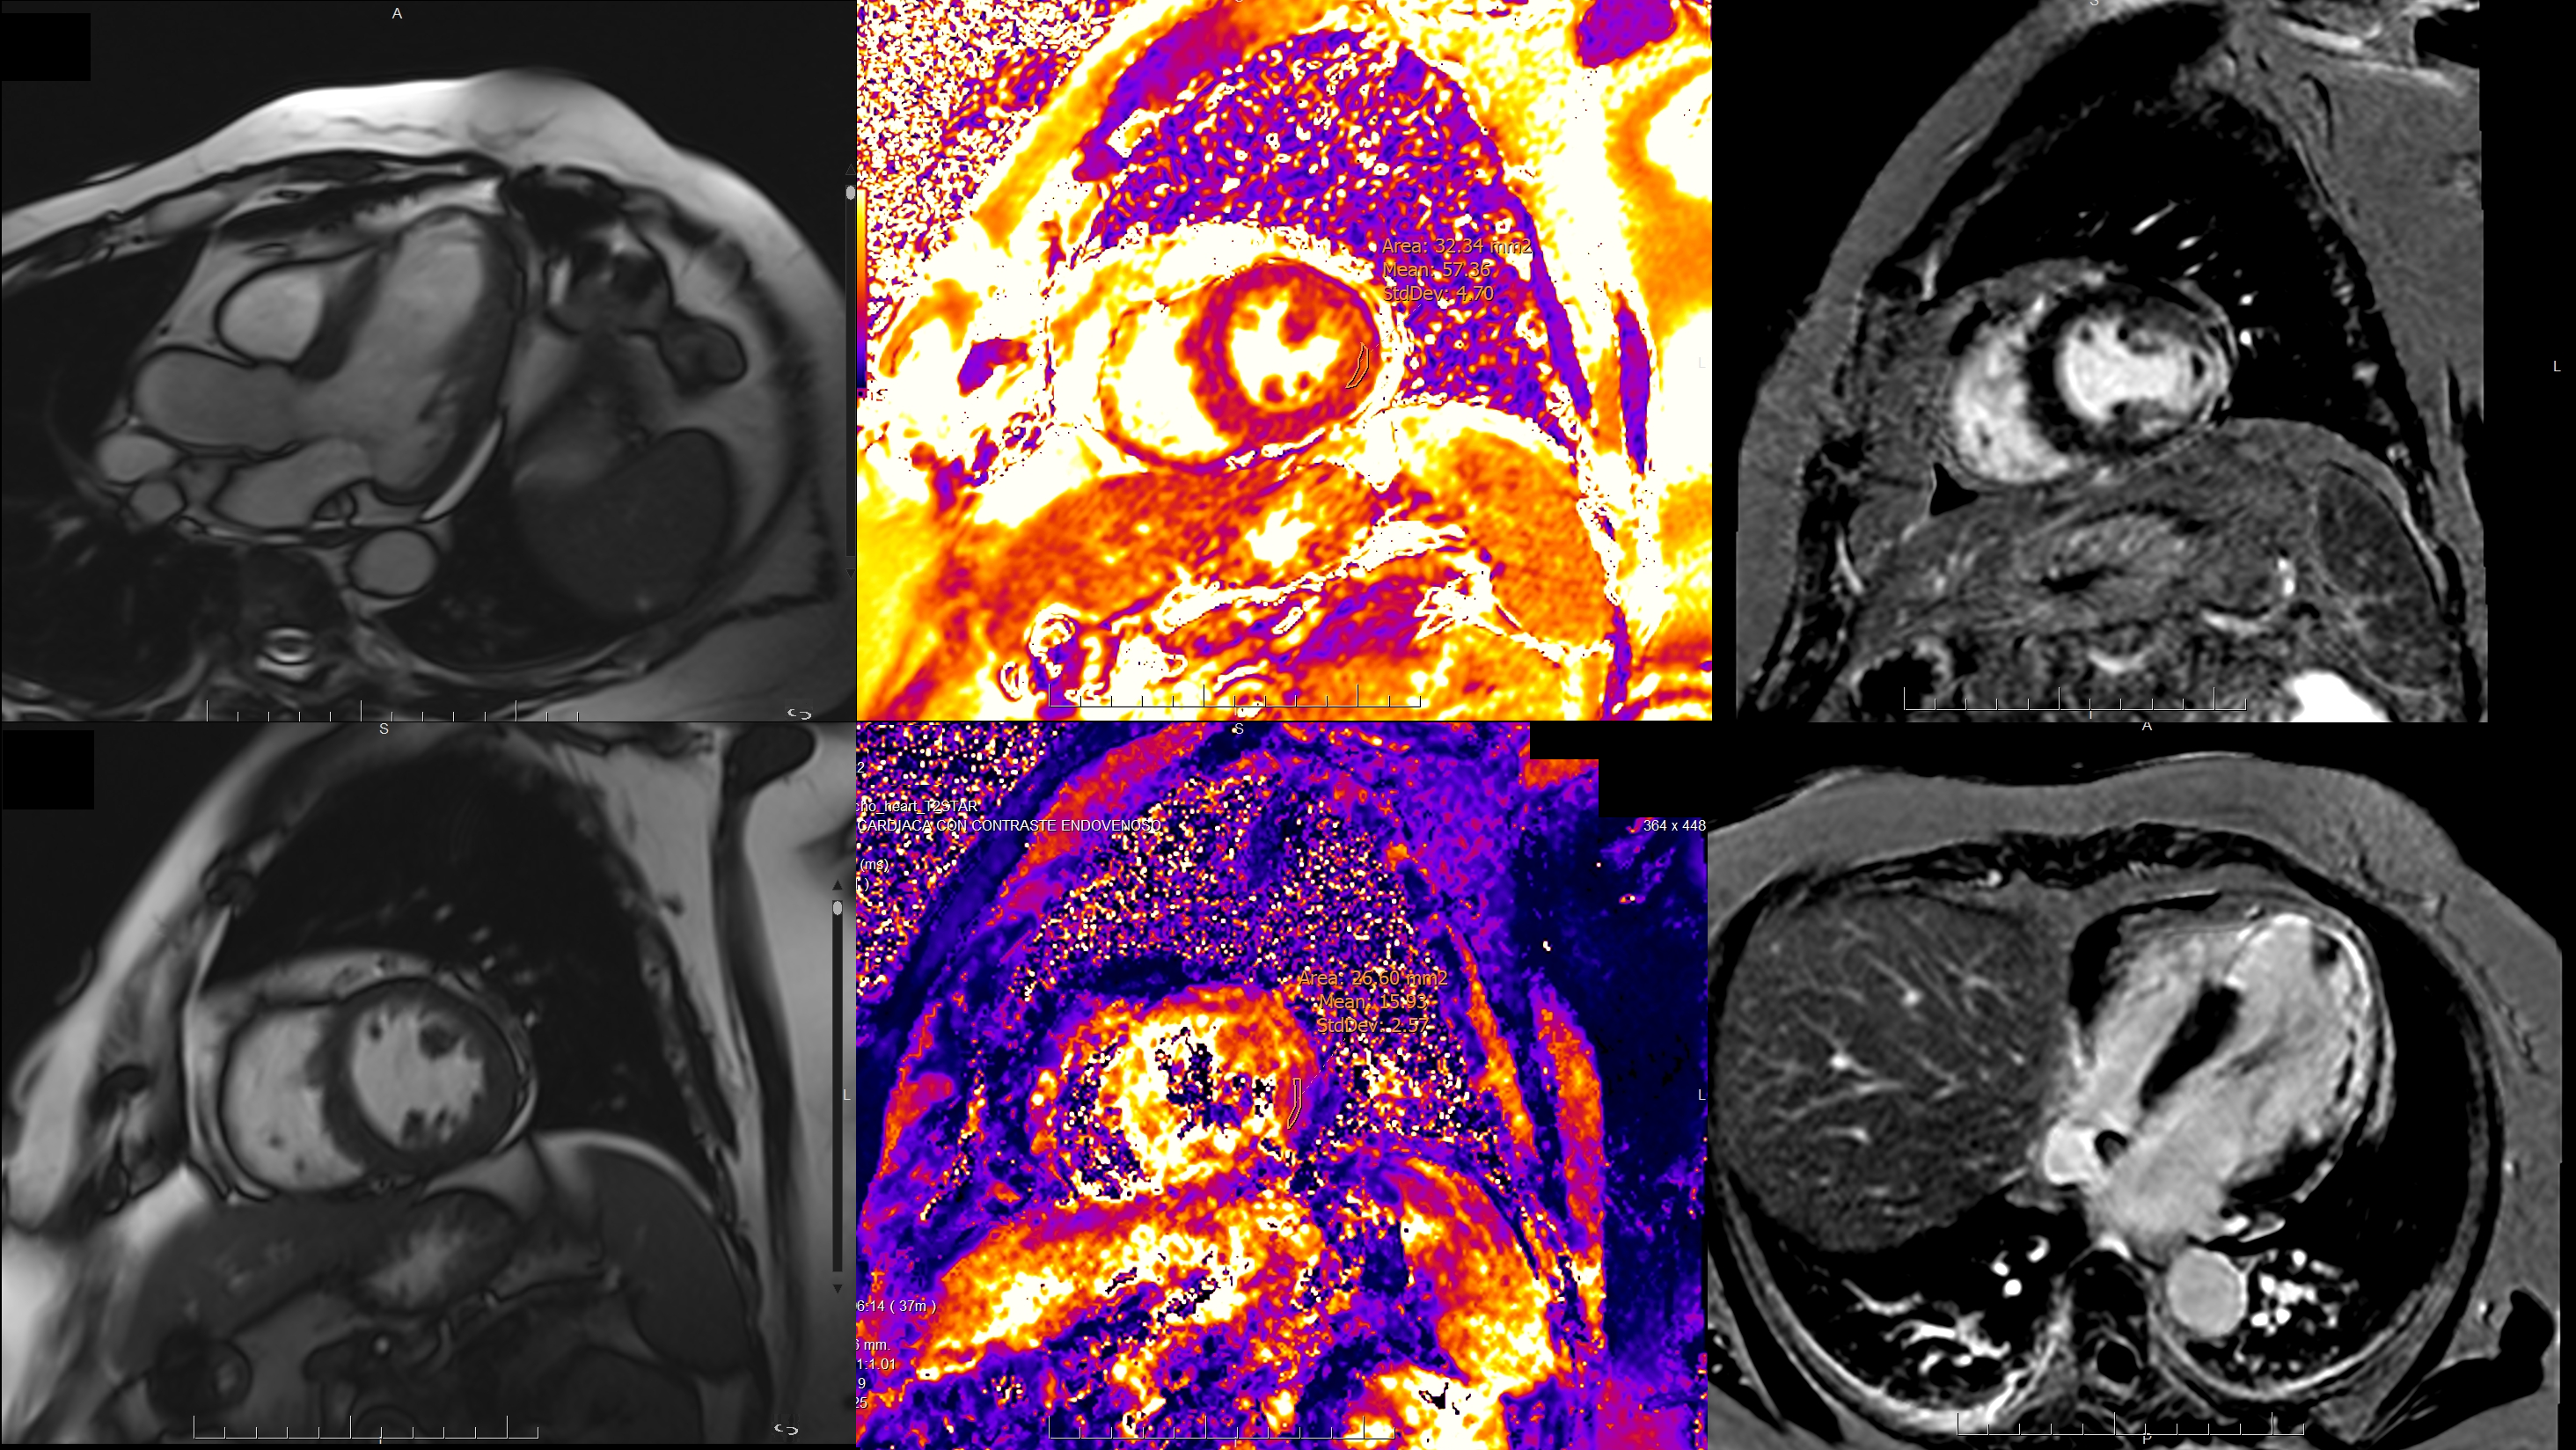

CMR was performed and revealed dyskinesia of the apical segments, inferolateral basal and inferomedial hypokinesia, inferolateral medial akinesia, and moderately reduced LVEF (45%). An apical aneurysmal expansion containing thrombus was present. Transmural LGE was observed in multiple apical and inferolateral segments. Microvascular obstruction was noted, and T2* mapping indicated intra-infarct hemorrhage.

Diagnostic Techniques and Their Most Important Findings: CMR revealed moderately reduced LV function (LVEF 45%) with inferior and inferolateral wall motion abnormalities, apical aneurysm, and thrombus. Initial angiography showed no significant stenosis. Elevated T1/T2 mapping values indicated myocardial edema and transmural LGE pattern confirmed acute infarction. T2* mapping revealed intramyocardial hemorrhage, a marker of adverse remodeling and poor prognosis

Figure 2. Coronary angiography showed no obstructive coronary lesions. Figure 3. CMR findings: apical aneurysm, microvascular obstruction, and mural thrombus in four-chamber view (LGE). Lateral wall edema (T2 mapping) and intra-infarct hemorrhage (T2* mapping) in short axis at mid-ventricular level and three-chamber view.

Figure 3. CMR findings: apical aneurysm, microvascular obstruction, and mural thrombus in four-chamber view (LGE). Lateral wall edema (T2 mapping) and intra-infarct hemorrhage (T2* mapping) in short axis at mid-ventricular level and three-chamber view.